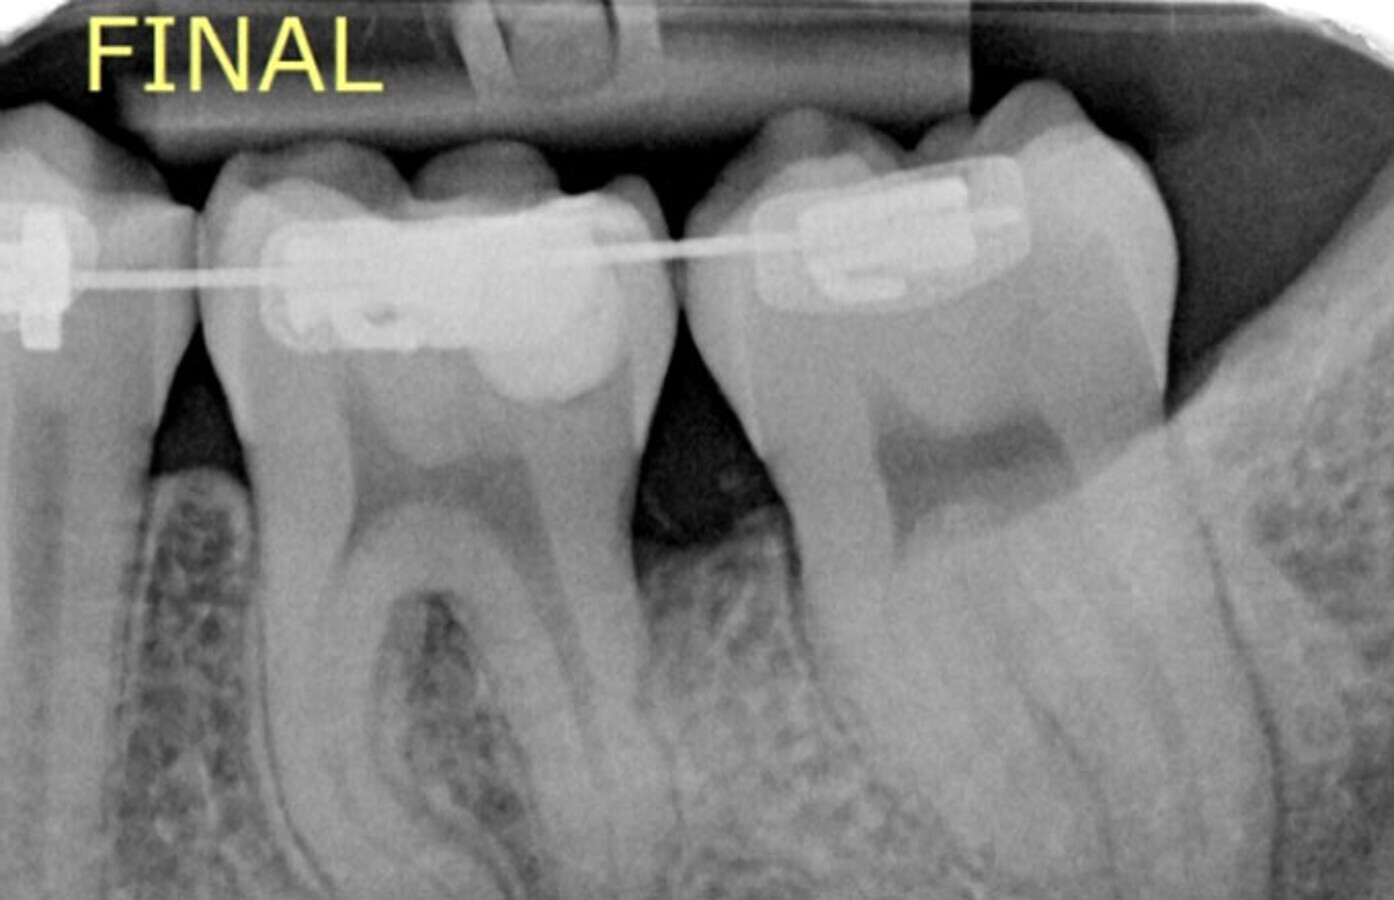

Radiografía final.

Aproximadamente 6 meses después, se prepara un anclaje esquelético con un tornillo de titanio autoperforante (D2.0 / L 12mm, Jeil Medical Corporation). Estos tornillos son más indicados para fijar injertos en bloque. Este anclaje permite enderezar el segundo molar por completo. En una primera fase, se tracciona desde el tornillo a un botón colocado en la cúspide distolingual del diente 37 con cadeneta elástica. Una vez el diente 37 está “desenclavado”, se termina de enderezar, cementando estratégicamente brackets y tubos de cementado directo y utilizando arcos elásticos NiTi.